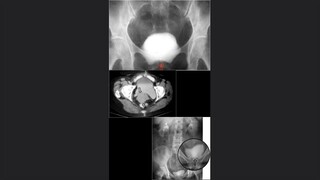

Vejiga